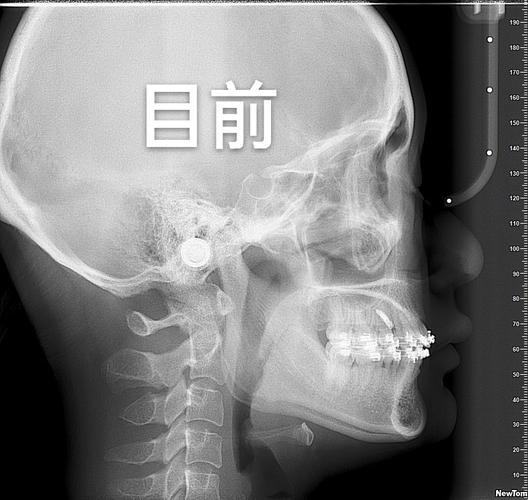

- 项目:口腔检查(视诊、探诊)、拍片(全景片、侧位片、CBCT,部分机构免费)、取模(传统或3D口扫);

- 目的:判断牙齿、牙槽骨、颌骨发育情况,评估是否需要拔牙、骨钉等辅助治疗。